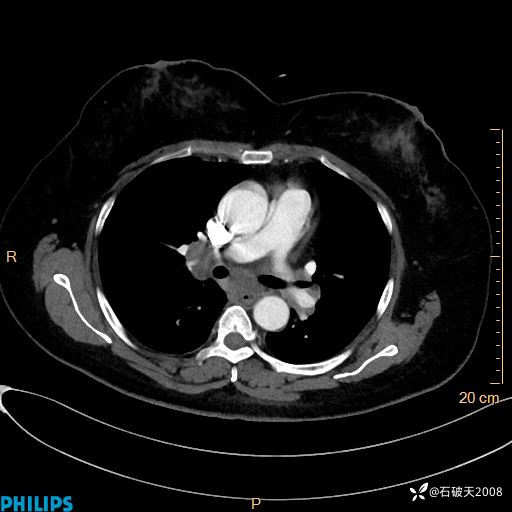

纵隔窗

动脉期